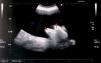

Since the first report in 1954, abdominal pseudocysts have been recognized as a particularly uncommon complication of ventriculoperitoneal shunts of CSF, so their etiology, diagnosis, and therapeutic management remain very controversial.

The clinical presentation of pseudocysts is normally through non-specific abdominal symptoms. The most validated etiology consists on the existence of a concomitant infection of the CSF shunt system, and so, treatment needs of antibiotherapy and total or partial substitution of the system. However, the pseudocyst itself doesn’t need an active treatment, except for some specific cases. This management, algorithmically presented in the present work, achieves a lower recurrence rate than other options, but this one is still important, and is also associated with other complications of those shunts related with several other factors which need to be taken in account.